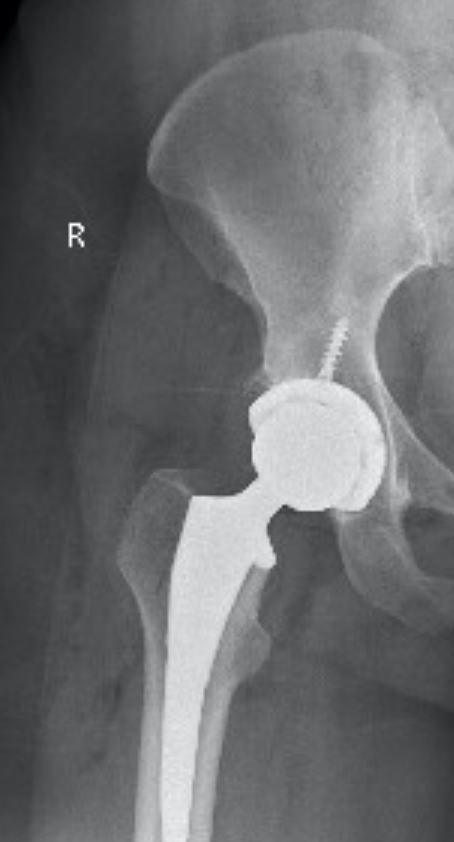

I’ve been recovering at home since August 16 (more on that later), but since this 7-year journey story is so long, I’ll pause here. I am grateful for my incredible family and friends, and for the 50-year-old imperfect hip that allowed me to have a wonderful life so far. And as for the new one, here she is. Hip, Hip Hooray!